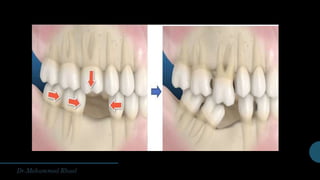

•Tilting : of neightbouring teeth

•Supra-eruption : of opposing teeth

PROBLEMS ASSOCIATED WITH MISSING TEETH •Thejaws may not “bite ”together properly, thus affecting the function of mastication/chewing •Pain na ot eud swaj/selcsum laicaf eht ni improper bite •Difficulty with speech •Aesthetically unpleasing yam selcsum laicaf eht sa‘ sag ’and gaps in the teeth might appear unsightly •Tilting : of neightbouring teeth •Supra-eruption : of opposing teeth •Food entrapment gnidael spag eht ni noitalumucca euqalp dna dna yaced erom ot gum disease •Last but not the least; your confidence gnitaeb a ekat thgim ni egnahc eht fo esuacebecnaraeppa